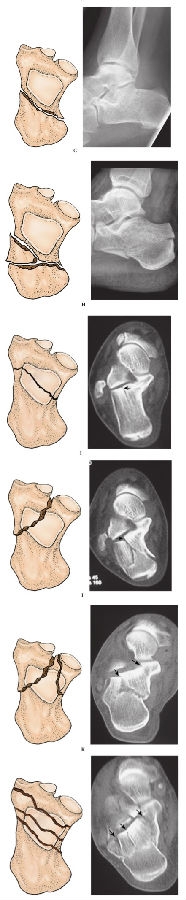

4、按解剖部位分型(图16):

图16 按解剖部位分型A.跟骨前突骨折;B.跟骨结节骨折;C.跟骨内侧突骨折;D.跟骨载距突骨折;E.跟骨体部骨折(不累及距下关节)

5、关节外骨折的混合分型(图17):

图17 关节外骨折的混合分型

1a:鸟嘴样骨折,不移位;

1b:跟腱附着处撕脱骨折;

1c:鸟嘴样骨折,移位;

2a,2b:跟骨内外侧突骨折;

3:载距突骨折;

4a:跟骨结节垂直骨折;

4b:骨骺撕脱骨折;

5a:前上撕脱或压缩骨折;

5b:跟骰关节骨折;

5c:远端下外侧骨折;

6a:趾伸肌腱撕脱骨折;

6b:跖筋膜撕脱骨折;

6c:后方关节囊的撕脱骨折。